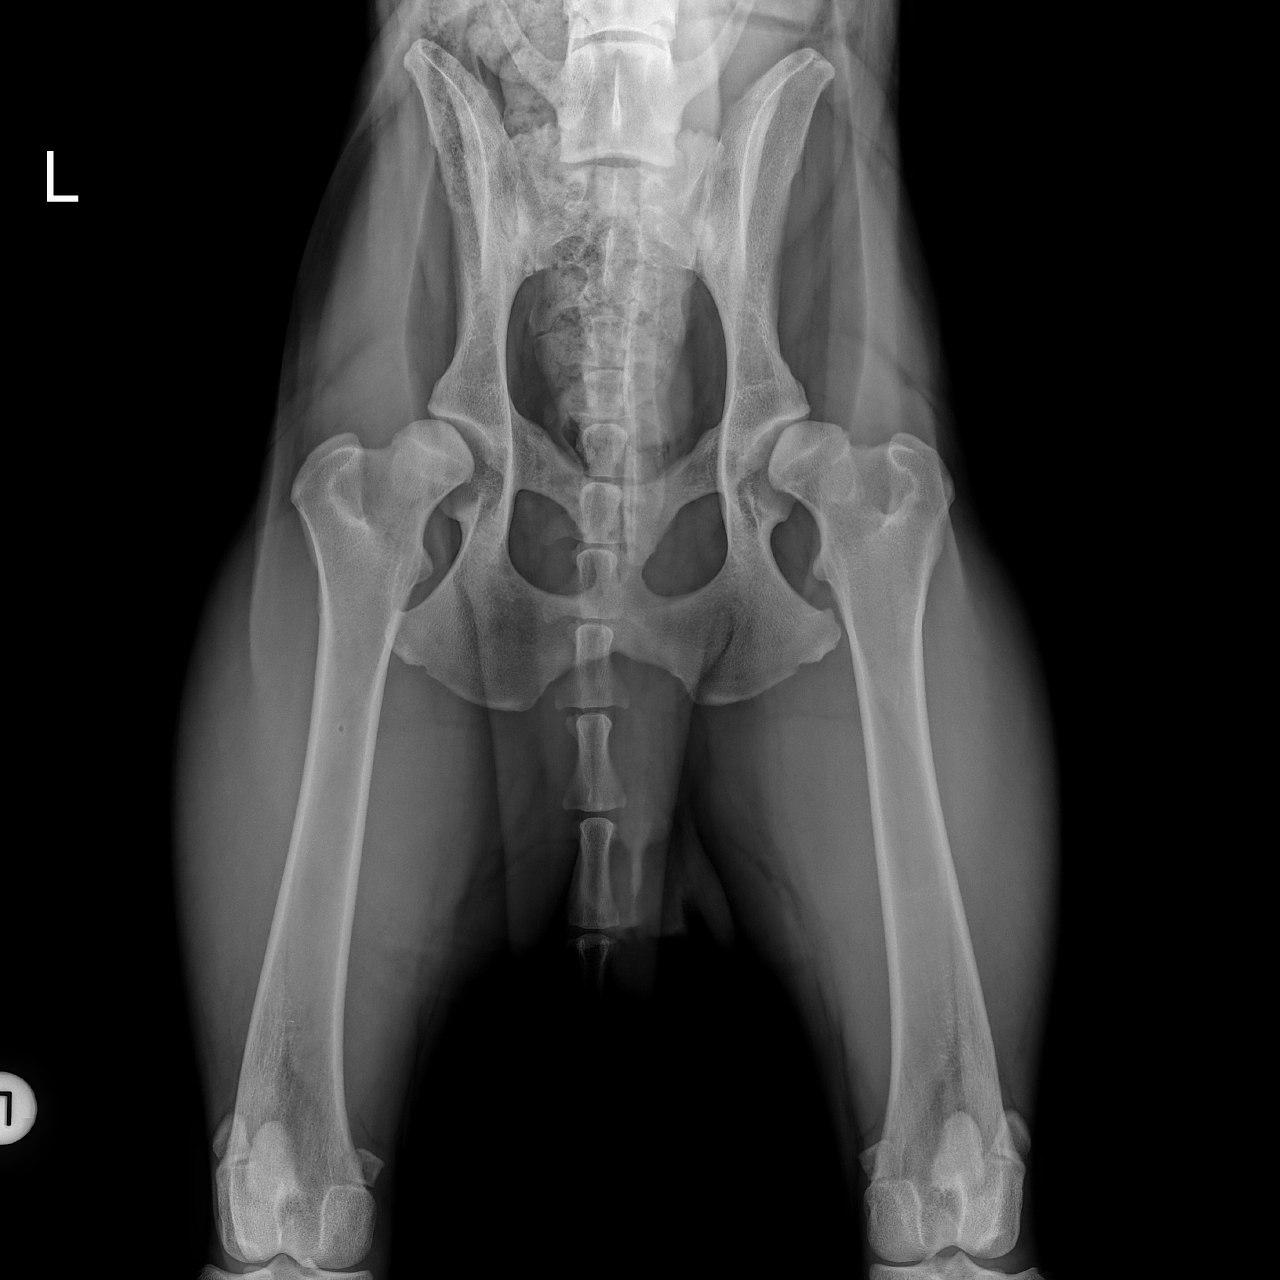

Mit der HD ist das so ne Sache..... die Vererbung spielt eine sehr große Rolle, ja. Aber bei unserer Peggy Zb ist es so, dass mehrere Generationen nachweislich HD und ED frei sind und auch frei von Spondylosen. Als einziger Hund überhaupt in der gesamten Zucht hat unsere Dame alles mitgenommen, was zu kriegen war;(: sie hat nicht nur schwere HD, weil ihre Hüfte viel zu locker ist, sondern dadurch bedingt am rechten Knie bereits schwere Arthrose und hinten links eine Sehenschwäche (durch Überlastung), weshalb sie dort durchtrittig ist. Und als würde das alles nicht schon vollkommen reichen, wurden aktuell auch noch mehrere heftige Spondylosen diagnostiziert;(. An einer Stelle ist sogar schon etwas abgebrochen8|.

Nun habe ich ein richtig gutes Gefühl gehabt: Hund vom netten Züchter, Elterntiere gecheckt und beide HD-frei und auch sonst top gesund.

Trotzdem hat er mittlere HD und ich fühle mich auch irgendwie total schuldig.

Leider reicht es halt nicht einfach nur zwei HD-freie Hunde miteinander zu verpaaren, um ausschließlich HD-freie Nachzucht zu erhalten. Wenn das so einfach wäre, dann wäre die HD seit Jahrzehnten bei allen Rassen ausgerottet. Durch eine entsprechende Zuchtselektion und eine hohe Röntgenquote bei der Nachzucht kann man das Risiko minimieren. Auf 0% bekommt man es aber leider nicht gesenkt.